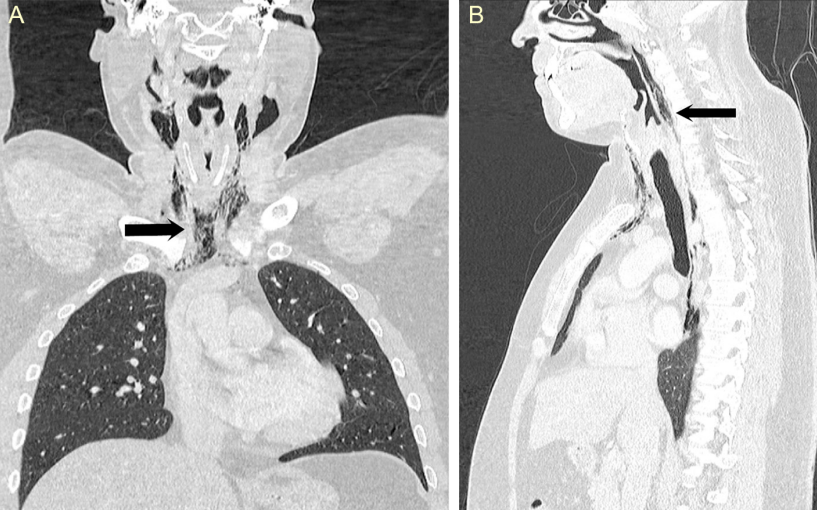

Симптомы начались после того, как мужчина сильно чихнул, несмотря на то, что старался сдержаться и для этого зажимал нос. Затем он начал жаловаться на острую боль, странный голос и припухлость шеи. Врачи обследовали мужчину, но не обнаружили никаких отклонений в легких и сделали рентгеновский снимок и компьютерную томографию. По снимкам стало ясно, что в шее и грудной клетке пациента имеется обширная эмфизема – скопление воздуха там, где его быть не должно. Диагноз гласил: спонтанный разрыв пищевода. После курса антибиотиков воспаление постепенно сошло на нет; во время лечения мужчина получал пищу через трубку, ведущую из носоглотки в желудок.